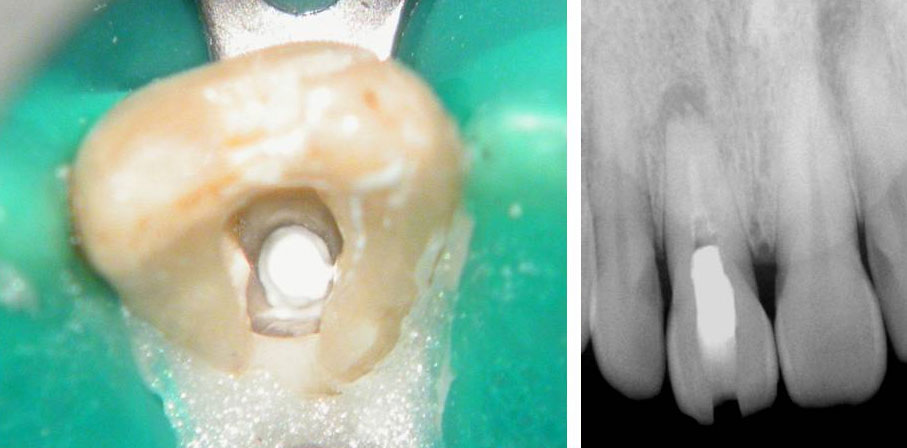

Residual caries seen after temp removal.

After caries removal

Cotton pellets placed over the palatal and Disto-buccal orifices to prevent the instrument from slipping into those canals.

Fractured instrument in mesio-buccal canal

Fractured instrument removed with ultrasonics

Canals cleaned, shaped and obturated

Fiberglass-post and composite core placed

Post-op